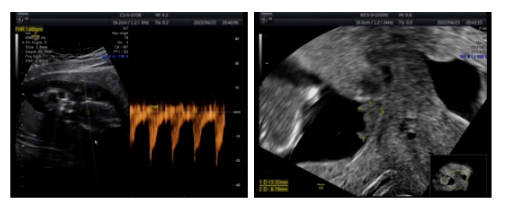

超声(2022-04-20)子宫右侧实性肿物——浆膜下肌瘤变性?

腹腔镜下子宫肌瘤剔除术(单孔)+卵巢扭转松解术

超声(2022-04-23):宫内孕活胎,羊水最大平面32mm,宫颈管闭合段长度34.2mm;盆腔后陷凹内液性暗区深约23mm。